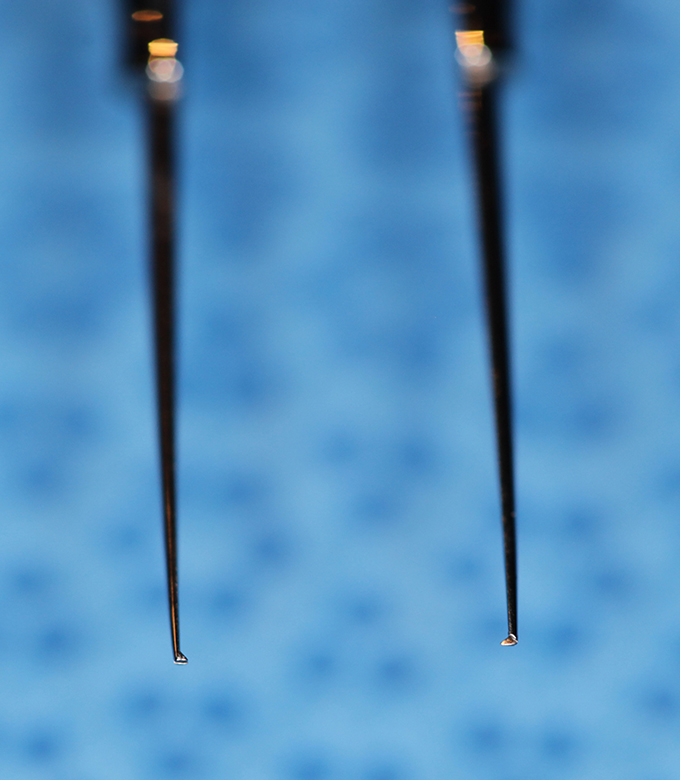

Bonn Forcep .12 Teeth - Enlarged

(aka Bonn Forceps)

catalog number: Storz E1809

Typical Use(s): Holding delicate tissue such as a scleral flap during glaucoma surgery; Has fine teeth smaller than classic .12 forceps